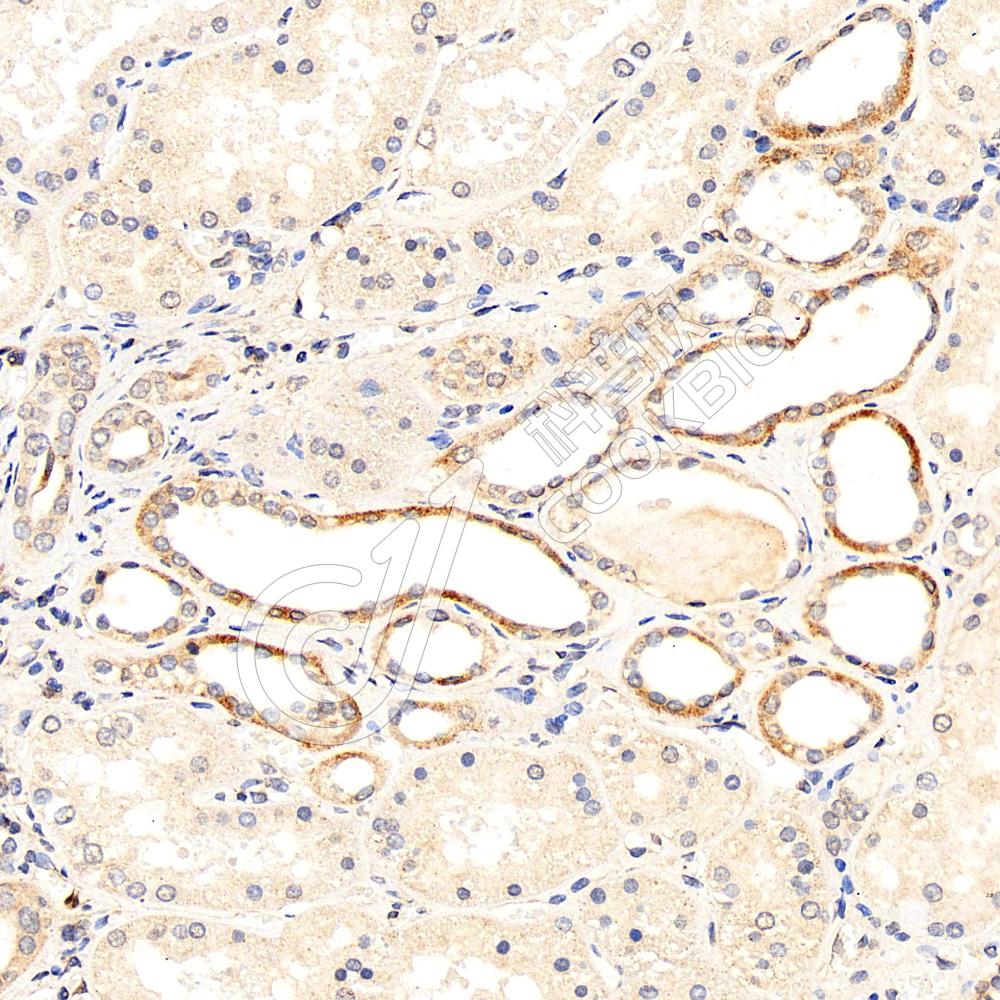

IHC检测MANEA蛋白(货号 K1342513).

样品: 人胎盘, 4%多聚甲醛 (货号KSG1101) 固定12-24小时.

抗原修复: 柠檬酸抗原修复液(干粉, pH 6.0) (KSG1201), 98℃, 20分钟.

—抗: 1: 1800稀释, 4℃ 孵育过夜.

二抗: S-vision免疫组化多聚二抗(山羊抗兔),即用型 (货号KB3906), 室温孵育20分钟.